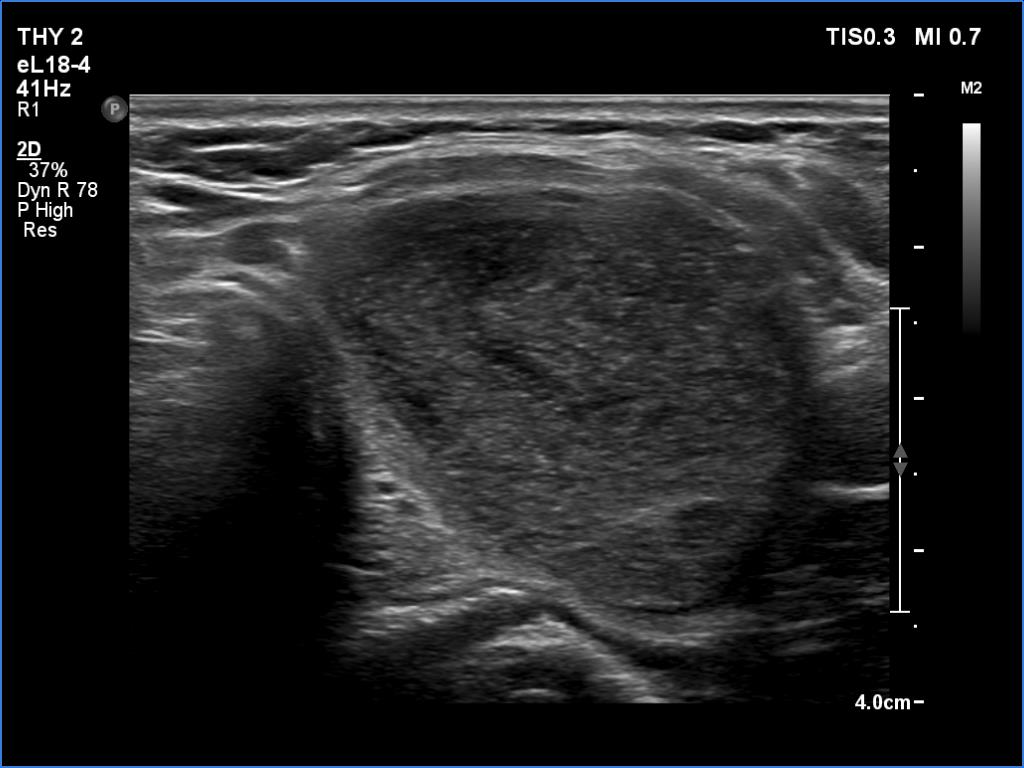

Ultrasonography. The thyroid was echonormal. There were several hypoechoic areas in the right lobe. The left lobe had a large minimally hypoechoic nodule with several tiny cystic areas. The lesion had numerous back wall figures.

In the first part of the ultrasound examination, when the transducer was continuously moving over the thyroid gland, it was not detectable that the contents of the nodule were showing flow. When we stopped the transducer, it became clear that the seemingly solid mass was actually a dense liquid in a continuous flow. On Doppler examination, 'circulation' was visible in continuously changing places.

This case illustrates two rare phenomena. On the one hand, a dense liquid may appear to be a solid tissue. On the other hand, the Doppler assay actually detects fluid flow. In the vast majority of cases, of course, this displays a circulation in the blood vessels, but in the case of cysts, when pressure is applied to the fluid with the probe, a flow is created. In the case of flow in blood vessels, circulation is always seen in the same place, while in the case of flowing cystic fluid, the flow can be detected in constantly changing places.